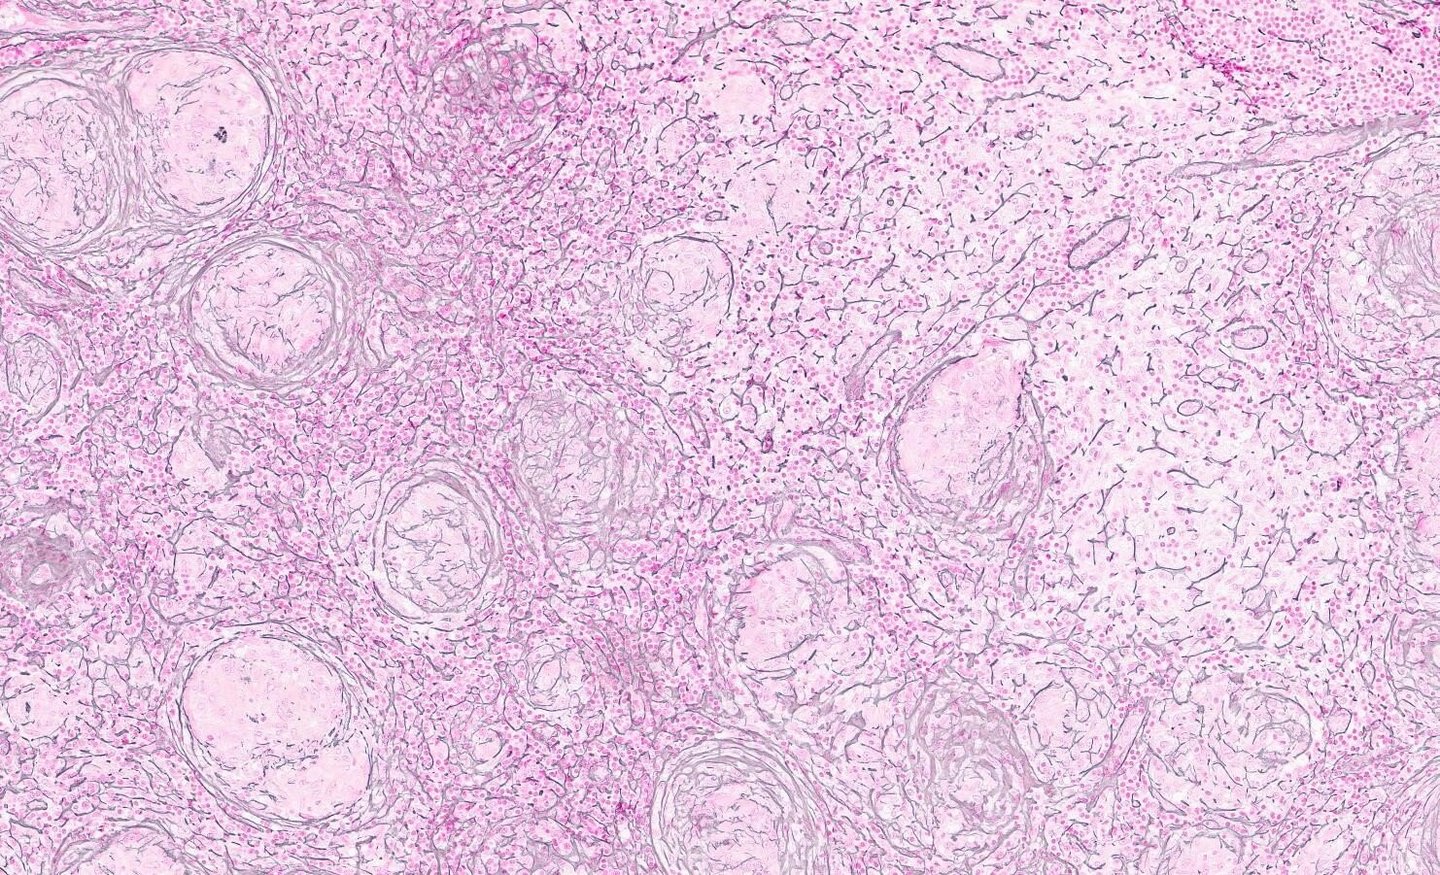

Solutions de pathologie numérique pour la confirmation des biomarqueurs et les collaborations

Tous nos blocs de tissus FFPE ayant fait l'objet d'une caractérisation génomique sont accompagnés d'images de lames H&E qui permettent de présélectionner vos blocs de tissus sur la base de données de biomarqueurs, garantissant ainsi que les échantillons sélectionnés contiennent ce dont vous avez besoin. Des images de lames entières sont disponibles pour tous les tissus sur demande via Proscia Concentriq.

Plus de 13 000 de nos blocs de tissus FFPE dans 15 indications oncologiques ont été séquencés par NGS et sont accompagnés de données sur les variantes, d'images de lames H&E et d'ADN/ARN isolés.